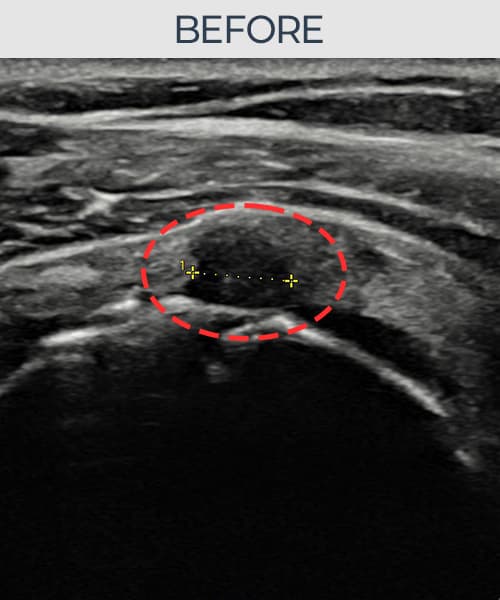

실제 환자의 시술 전후 초음파 영상입니다.

수술 없이 이뤄낸 회복을 직접 확인하세요.

모든 초음파 영상은 실제 환자의 동의를 받아 게시하였습니다. 개인차가 있으며 동일한 결과를 보장하지 않습니다.

[촬영시기:23.07.31~23.09.27]

[어깨인대 축소봉합술] 좌측 어깨 극상근건 광범위 파열로 수개월간 일상생활이 어렵던 중 내원하셨습니다.